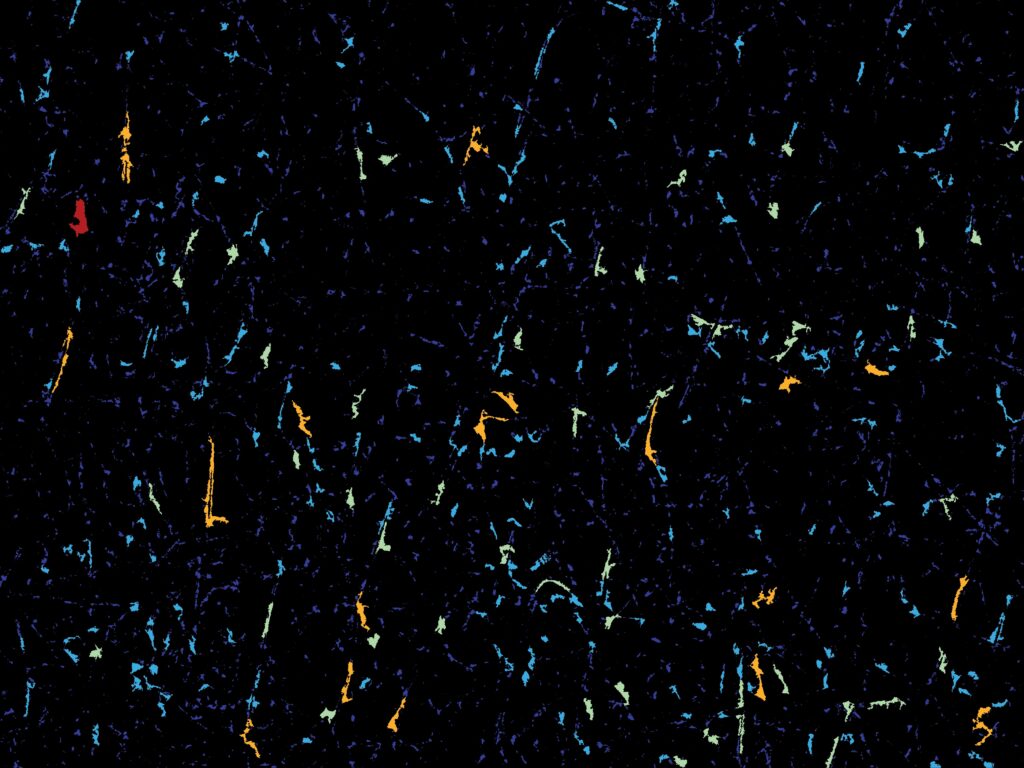

100% automated hair analysis using AI segmentation

Thanks to advanced AI-powered segmentation algorithms, the C-Cube now enables fully automated detection of hair fibers in the image.

Each hair is individually identified, which allows for:

-

automatic diameter calculation,

-

measuring hair length and regrowth,

-

quantification of density.

This automation reduces analysis time, minimizes operator variability, and ensures optimal reproducibility in longitudinal studies.